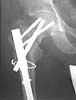

We fluoroscoped every thing in the OR under anesthesia. It was clear that the Ltproximal side is unstable, in mal-position and the nail is probably outproximally.

On the Rt side, the proximal construct was stable but the distal (the shaft fx)was not.

AP Pelvis

Lt femur

Rt femur

Lt hip

Rt hip

Lt leg incisions

We decided to fix the Lt femur with a few lag screws on the proximal part andstabilize the femur with long Richard plate that was inserted in a sub-muscularfashion, in order to avoid opening the main shaft fx (the so-called biologicfixation - see Lt leg incisions.).

On the Rt side I replaced the recon nail with a longer one (accepting its toolateral and anterior entering point), I added a proximal locking screw (anterior toposterior) in the subtrochanteric region through a self-made extra hole, and two 6.5cancellous hip screws posterior to the nail.